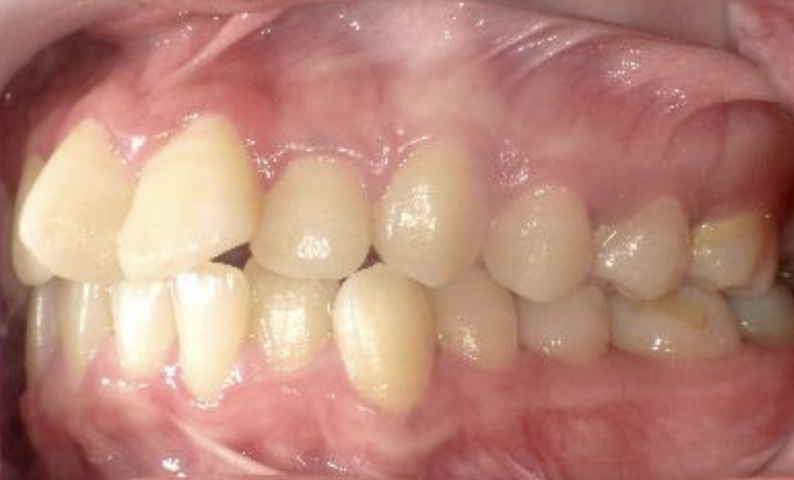

症例_023 上顎だけの部分矯正

治療期間:9ヶ月金額:30万円+税女性前歯のガタガタ上の前歯だけ

| Before | After |

|---|---|

|